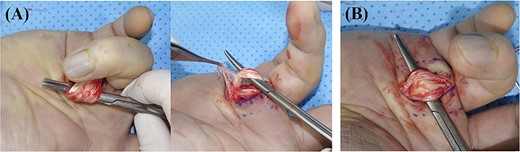

During the operation, the 1.5 cm-sized mass was excised through the longitudinal incision on A1 pulley area. This mass was well defined and encapsulated, and it was tightly attached to the A1 pulley (Fig. 2). There was severe tenosynovitis around flexor tendon and severe adhesion between flexor digitorum superficialis and profundus. Extensive tenosynovectomy around and between flexors was performed. Flexor tendon had a severe splitting lesion (Fig. 3). We considered the possibility of tuberculosis tenosynovitis and performed mycobacterial culture and biopsy. However, histological examination revealed a simple benign fibrous nodule, and there was no evidence of tuberculosis infection.

The encapsulated mass was excised through a longitudinal incision; the mass was surrounded with inflammatory tissue.